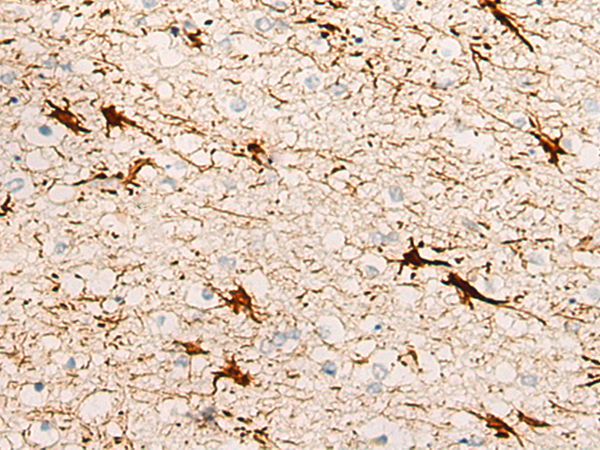

分类: 科研抗体货号: P13239别名:应用: IHC反应种属: Human